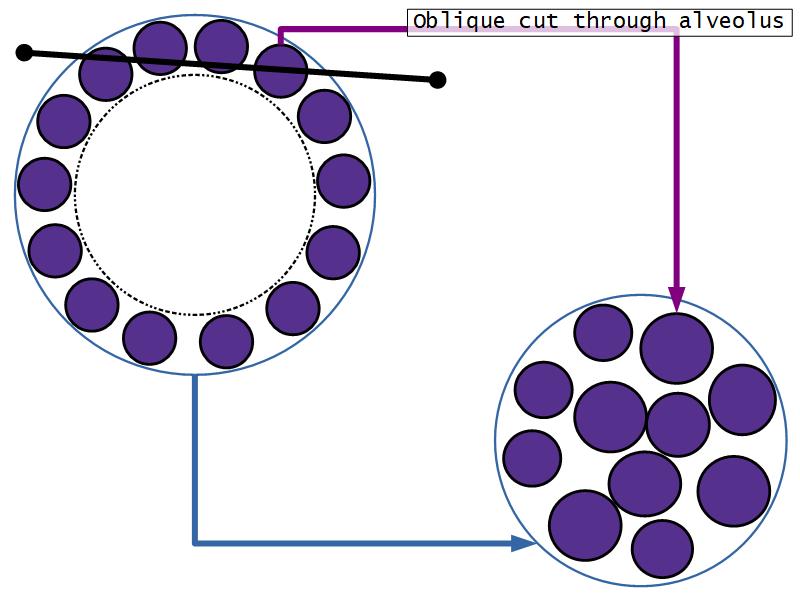

Active gland

- Much larger than resting phase

- Terminal ducts proliferate to form alveoli

- Alveoli

- Surrounded by incomplete myoepithelial cells